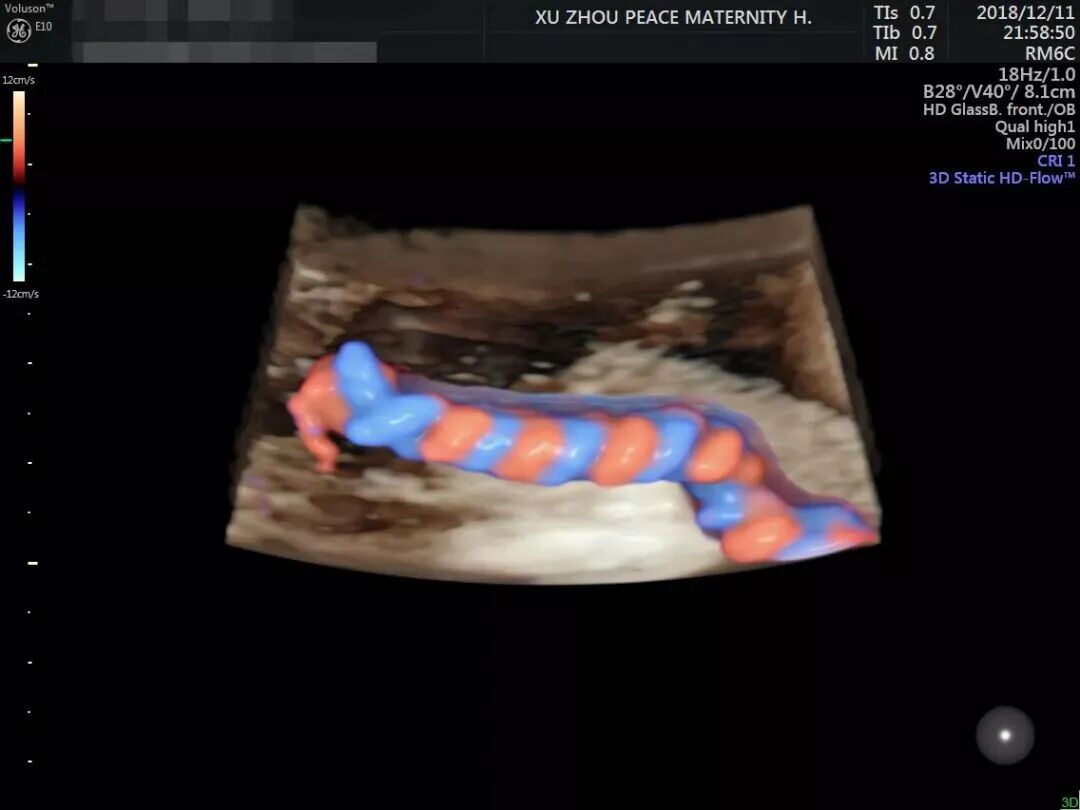

邱博士高清超声成像精彩画面(滑动查看更多)

UOG杂志刊登的邱博士胎盘血管影像资料

(滑动查看更多)